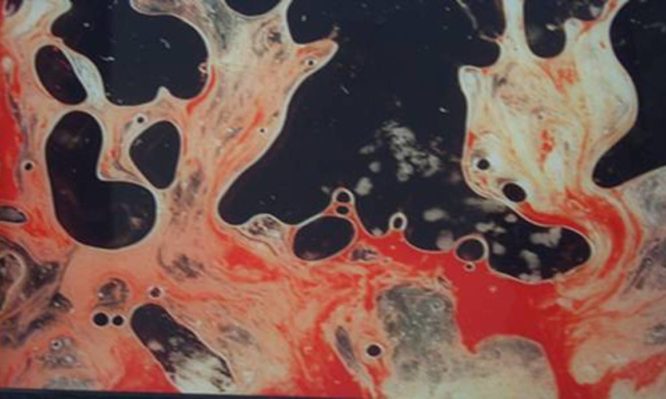

Τι πρέπει να κάνουμε όταν δούμε αίμα στο σπέρμα μας;

Σίγουρα το να δει κάποιος άνδρας αίμα στο σπέρμα του, θα τον ανησυχήσει, μην σας πούμε ότι θα τον...

Σίγουρα το να δει κάποιος άνδρας αίμα στο σπέρμα του, θα τον ανησυχήσει, μην σας πούμε ότι θα τον...